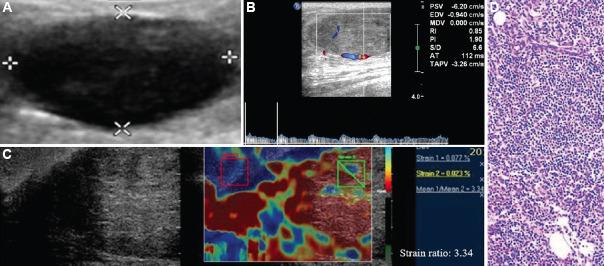

BACKGROUND & OBJECTIVES: : Ultrasound BI-RADS categories 3 and 4 constitute those breast masses which cannot be confidently classified as benign or malignant, owing to their morphological characteristics. These masses are further managed by follow up and biopsy, respectively. This study aims to evaluate the role of strain elastography and Doppler in better characterization of these sonographically indeterminate breast masses as benign or malignant.

: Fifty female patients with ultrasound BI-RADS 3 or 4 were evaluated with strain elastography and color Doppler including spectral analysis. Eight variables were assessed by elastography and Doppler, including a new phenomenon called bidirectional arterial flow (BAF). The findings were correlated with the gold standard diagnostic method of histopathology/cytology. Based on findings of combined elastography and Doppler method, the initial ultrasound BI-RADS categories of masses were re-categorized by up-gradation or down-gradation. Sensitivity, specificity, accuracy, positive predictive value, negative predictive value and receiver operating characteristic (ROC) curves were used to estimate the diagnostic performance of the combination method.

: Using ROC analysis, the positivity of ≥3 among the total eight variables correlated with malignancy on histopathology. Sensitivity, specificity and accuracy of the combination method using cut-off score ≥3 (i.e. at least three out of the eight parameters in the combination method being positive) for the prediction of malignancy was 100, 76.47 and 92 per cent, respectively, with the area under curve being 0.967. In addition, BAF was found predictive of malignancy with a diagnostic accuracy of 70 per cent.